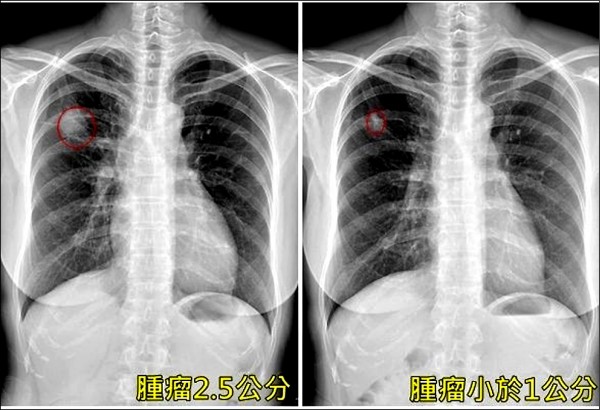

根據《TVBS新聞網》報導,近期藝壇大咖顏正國因肺腺癌離世,再度引發社會各界對於肺癌議題的關注。台灣的肺癌死亡率連續43年高居首位,更令人憂心的是,女性患者人數持續攀升,且大部分並非因吸菸或長期烹調所致。

台大醫院外科部主任陳晉興在專訪中指出,國內肺腺癌患者中,不吸菸者的比例竟然超過吸菸者。這種癌症與上皮細胞生長因子受體基因(EFGR)突變息息相關,一旦發生基因變異,不僅容易引發細胞癌變,還可能擴散至其他器官,導致病情惡化。